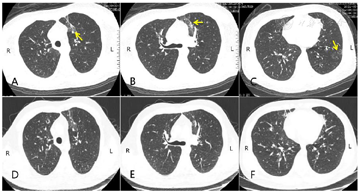

治疗期间患者病情演变(图2),多次复查胸部X线片(图3),10天后好转。随访患者哮喘控制症状、胸部CT(图4)及肺功能(图5)。检查局限性:患者病情危重,由于ECMO仪器特殊性及管路因素,未完善肺功能及胸部CT检查。

1周后第一次随访,患者哮喘症状控制良好,复查胸部CT及肺功能(极重度阻塞性通气功能障碍)。3周后第二次随访,患者未诉哮喘症状,并再次复查胸部CT及肺功能(通气功能基本正常)。3个月后电话随访,患者仍进行奥马珠单抗治疗,并规律吸入沙美特罗替卡松气雾剂,症状控制良好。